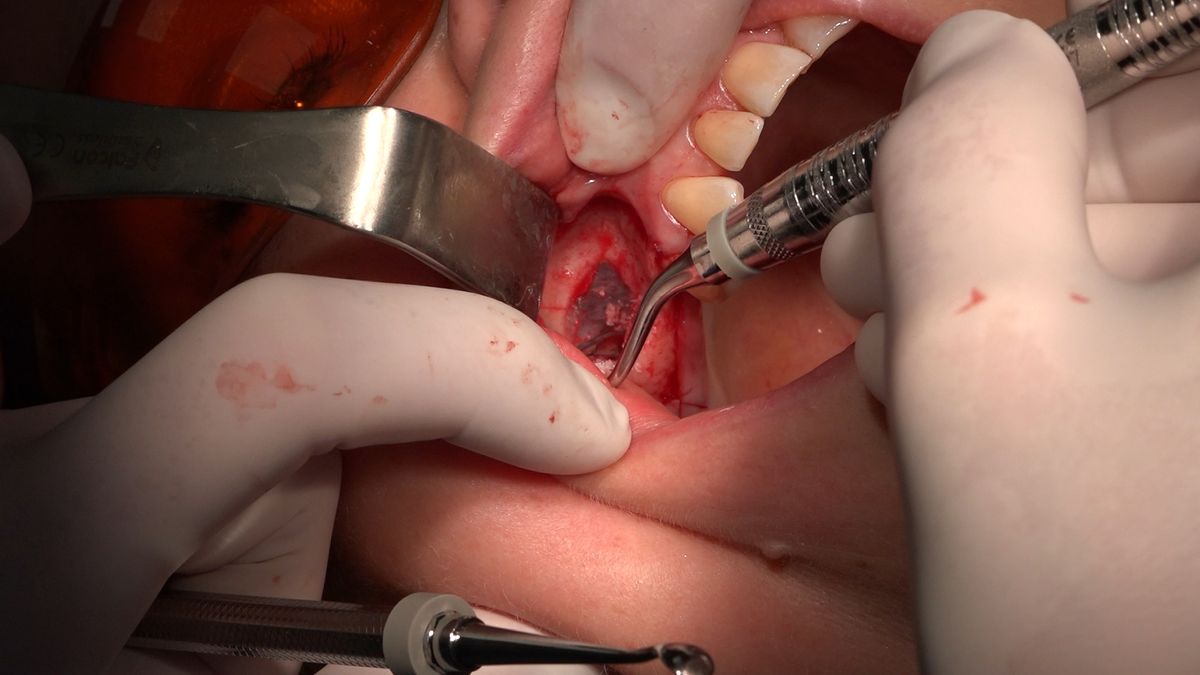

Practiculum Implantologii – Sezon VIIB, sesja 7, dzień 2